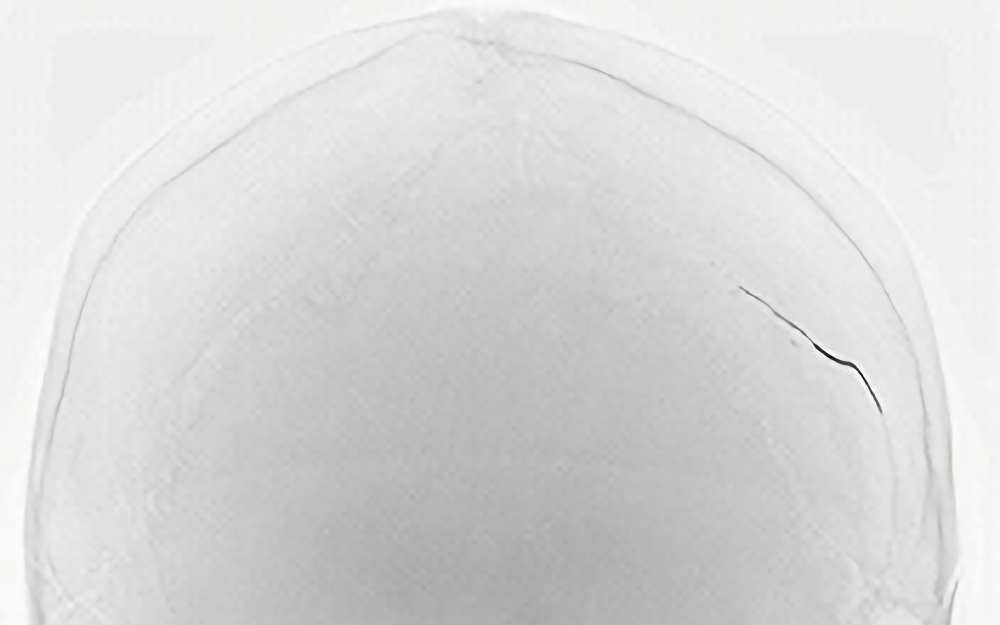

No.1023 手術前